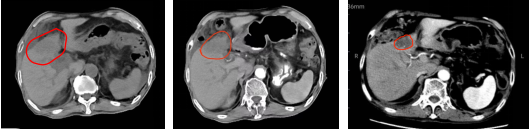

病例展示二:胆管恶性肿瘤

肝内胆管癌,肝S4段占位(47mm x35mm x37mm),病灶累及胆囊及肝门部胆管、左肝管扩张。病理诊断(病理号:829802):中分化腺癌。cT4N1M0 IIIB期。治疗方案:碳离子放疗,总剂量:PTV 68.4Gy(RBE)/18Fx,同步靶向治疗:芦康沙妥珠单抗 200mg q3w,长期疗效达持续缓解。

(治疗前)2025-04-23 (治疗2周)2025-5-7 (治疗后4月)2025-09-26